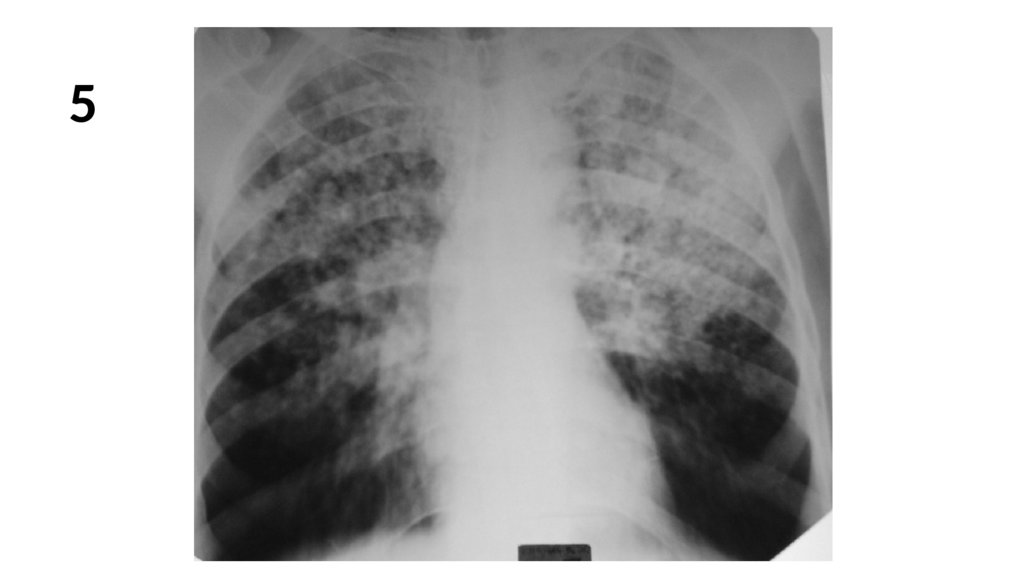

5.

5